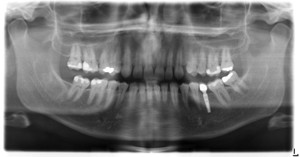

Zahnimplantate sind eine sehr elegante und zeitgemässe Lösung, um fehlende Zähne zu ersetzen. Von der Einzelzahnlücke bis zum zahnlosen Kiefer sind Implantate einsetzbar.